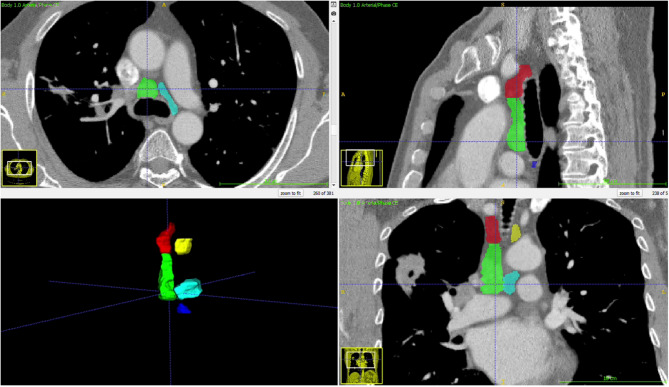

Methods: We retrospectively analyzed 1489 patients who underwent standard cervical mediastinoscopy at our department, including 472 patients diagnosed with non-small cell lung cancer. We developed three distinct prediction models for N2 lymph node station metastasis: one using standard statistical analysis, another utilizing an image processing deep learning algorithm with thoracic CT, and the third employing various machine learning methods with clinicopathological and radiological data. We compared diagnostic accuracy, area under the curve (AUC), sensitivity, and specificity rates, as well as the F1-score of all models.